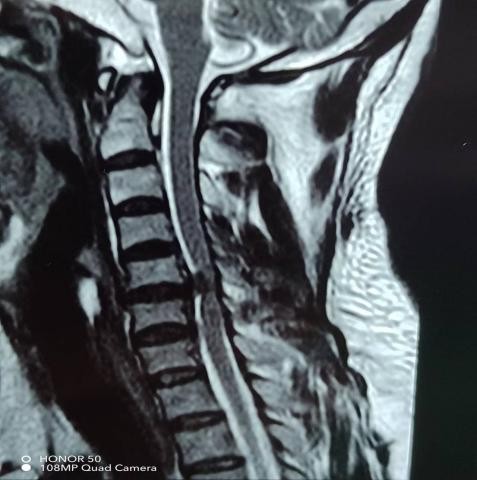

近期,年轻的阿明突然出现一侧肢体无力,开始家人以为“脑中风”,后明确原来为颈椎病椎间盘急性脱出,在广东省人民医院(下称“省人医”)帮扶下,我院骨科予以手术治疗,效果良好,手术后3天顺利出院,患者及家属对医生表示了由衷的感谢!